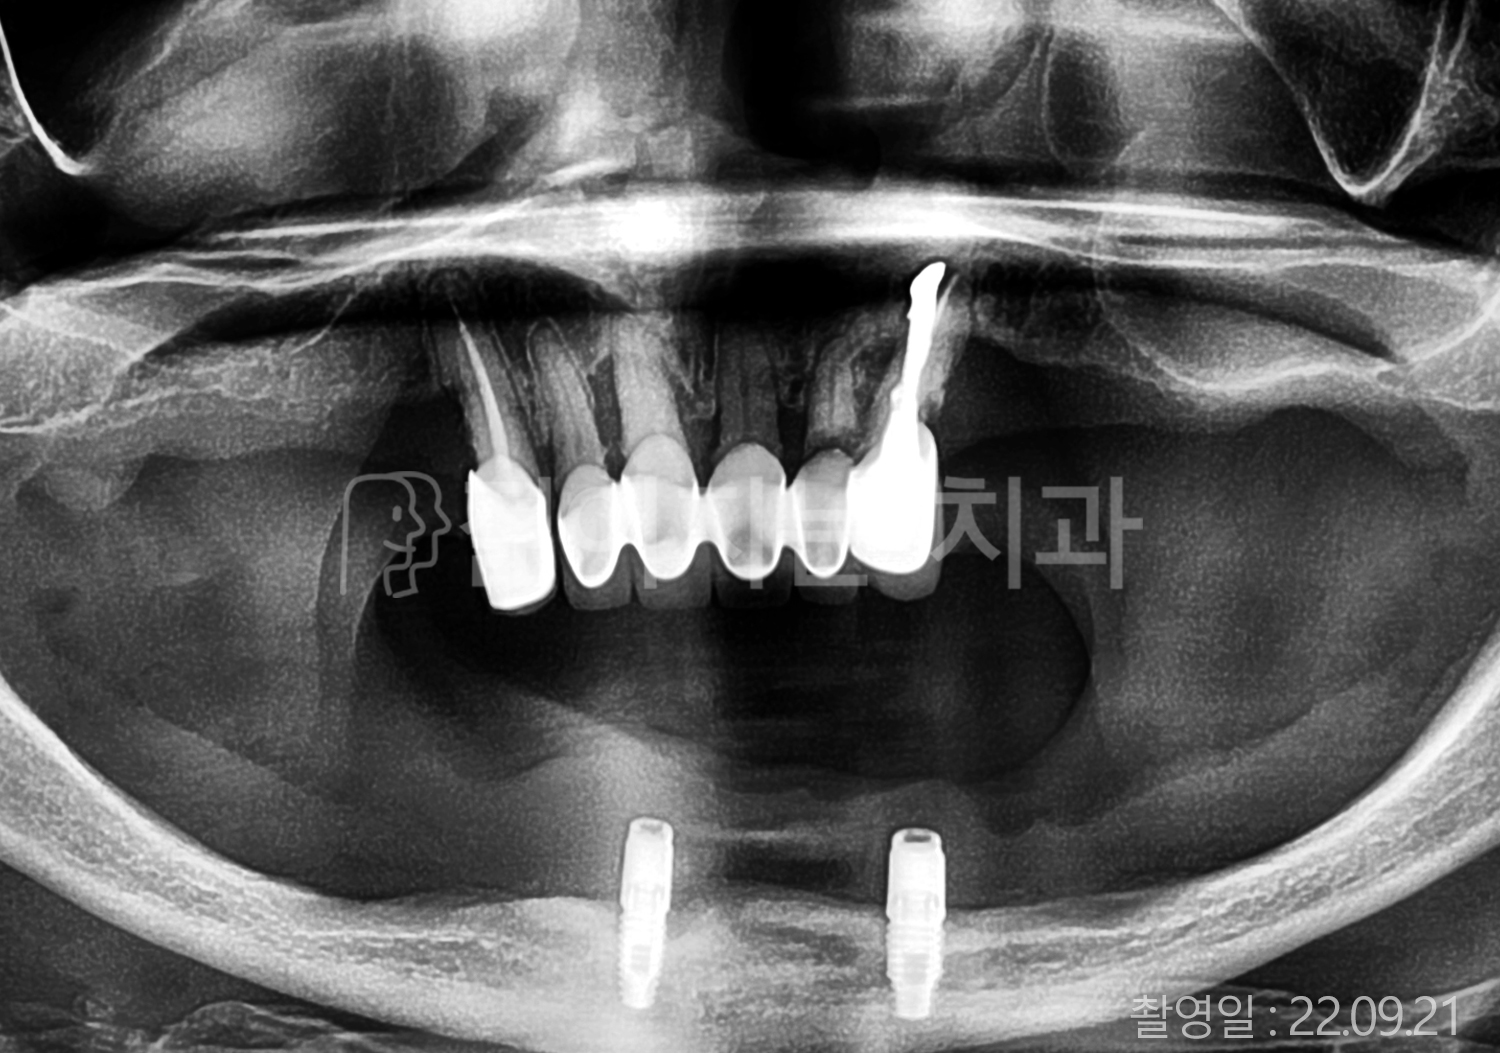

• 50대 고혈압, 당뇨, 고지혈증 전체치아 10개 이상 임플란트

• 60대 골다골증, 간경화 전체치아 10개 이상 임플란트

• 60대 고혈압, 고지혈증 전체치아 10개 이상 임플란트

• 50대 고혈압, 당뇨 전체치아 10개 이상 임플란트